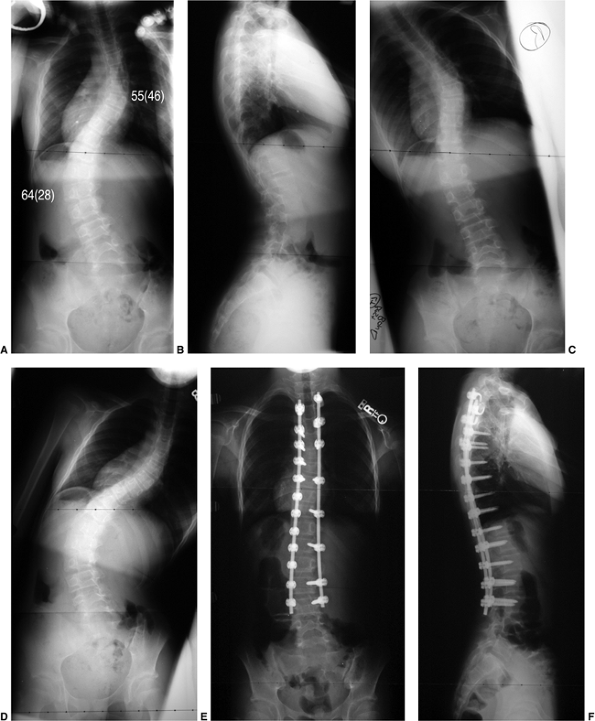

Figure 18.4 A: This posteroanterior radiograph demonstrates the appearance of a double thoracic scoliosis curve pattern. B:

The lateral radiograph demonstrates the relatively straight sagittal profile of the thoracic spine with loss of normal thoracic kyphosis. This is a common feature of adolescent idiopathic scoliosis. C: The clinical appearance of this patient demonstrates a prominent scapula. However, this is not caused by kyphosis but by the rotational deformity of the ribs, which secondarily makes the right scapula more prominent. Additionally, a left upper thoracic trapezial fullness can be appreciated in this patient, caused by the left upper thoracic curvature.  |